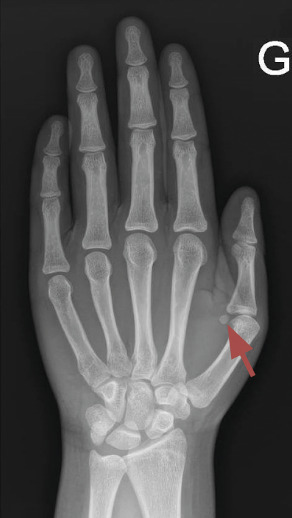

La maturation osseuse est évaluée grâce à une radiographie de la main gauche et du poignet gauche selon la méthode de Greulich et Pyle : c’est l’âge osseux.

Un âge osseux (fig. 4) est réalisé pour confirmer une avance de maturation osseuse. Chez les filles, une échographie pelvienne peut rechercher une imprégnation des organes génitaux internes (augmentation de la hauteur utérine > 35 mm et modification de la morphologie). L’échographie est aussi indiquée pour éliminer une tumeur surrénalienne ou ovarienne, ou des kystes ovariens. En cas de puberté précoce centrale, il convient de réaliser une IRM de la région hypothalamo-hypophysaire. Une imagerie des gonades est en revanche nécessaire dans un contexte de puberté périphérique.